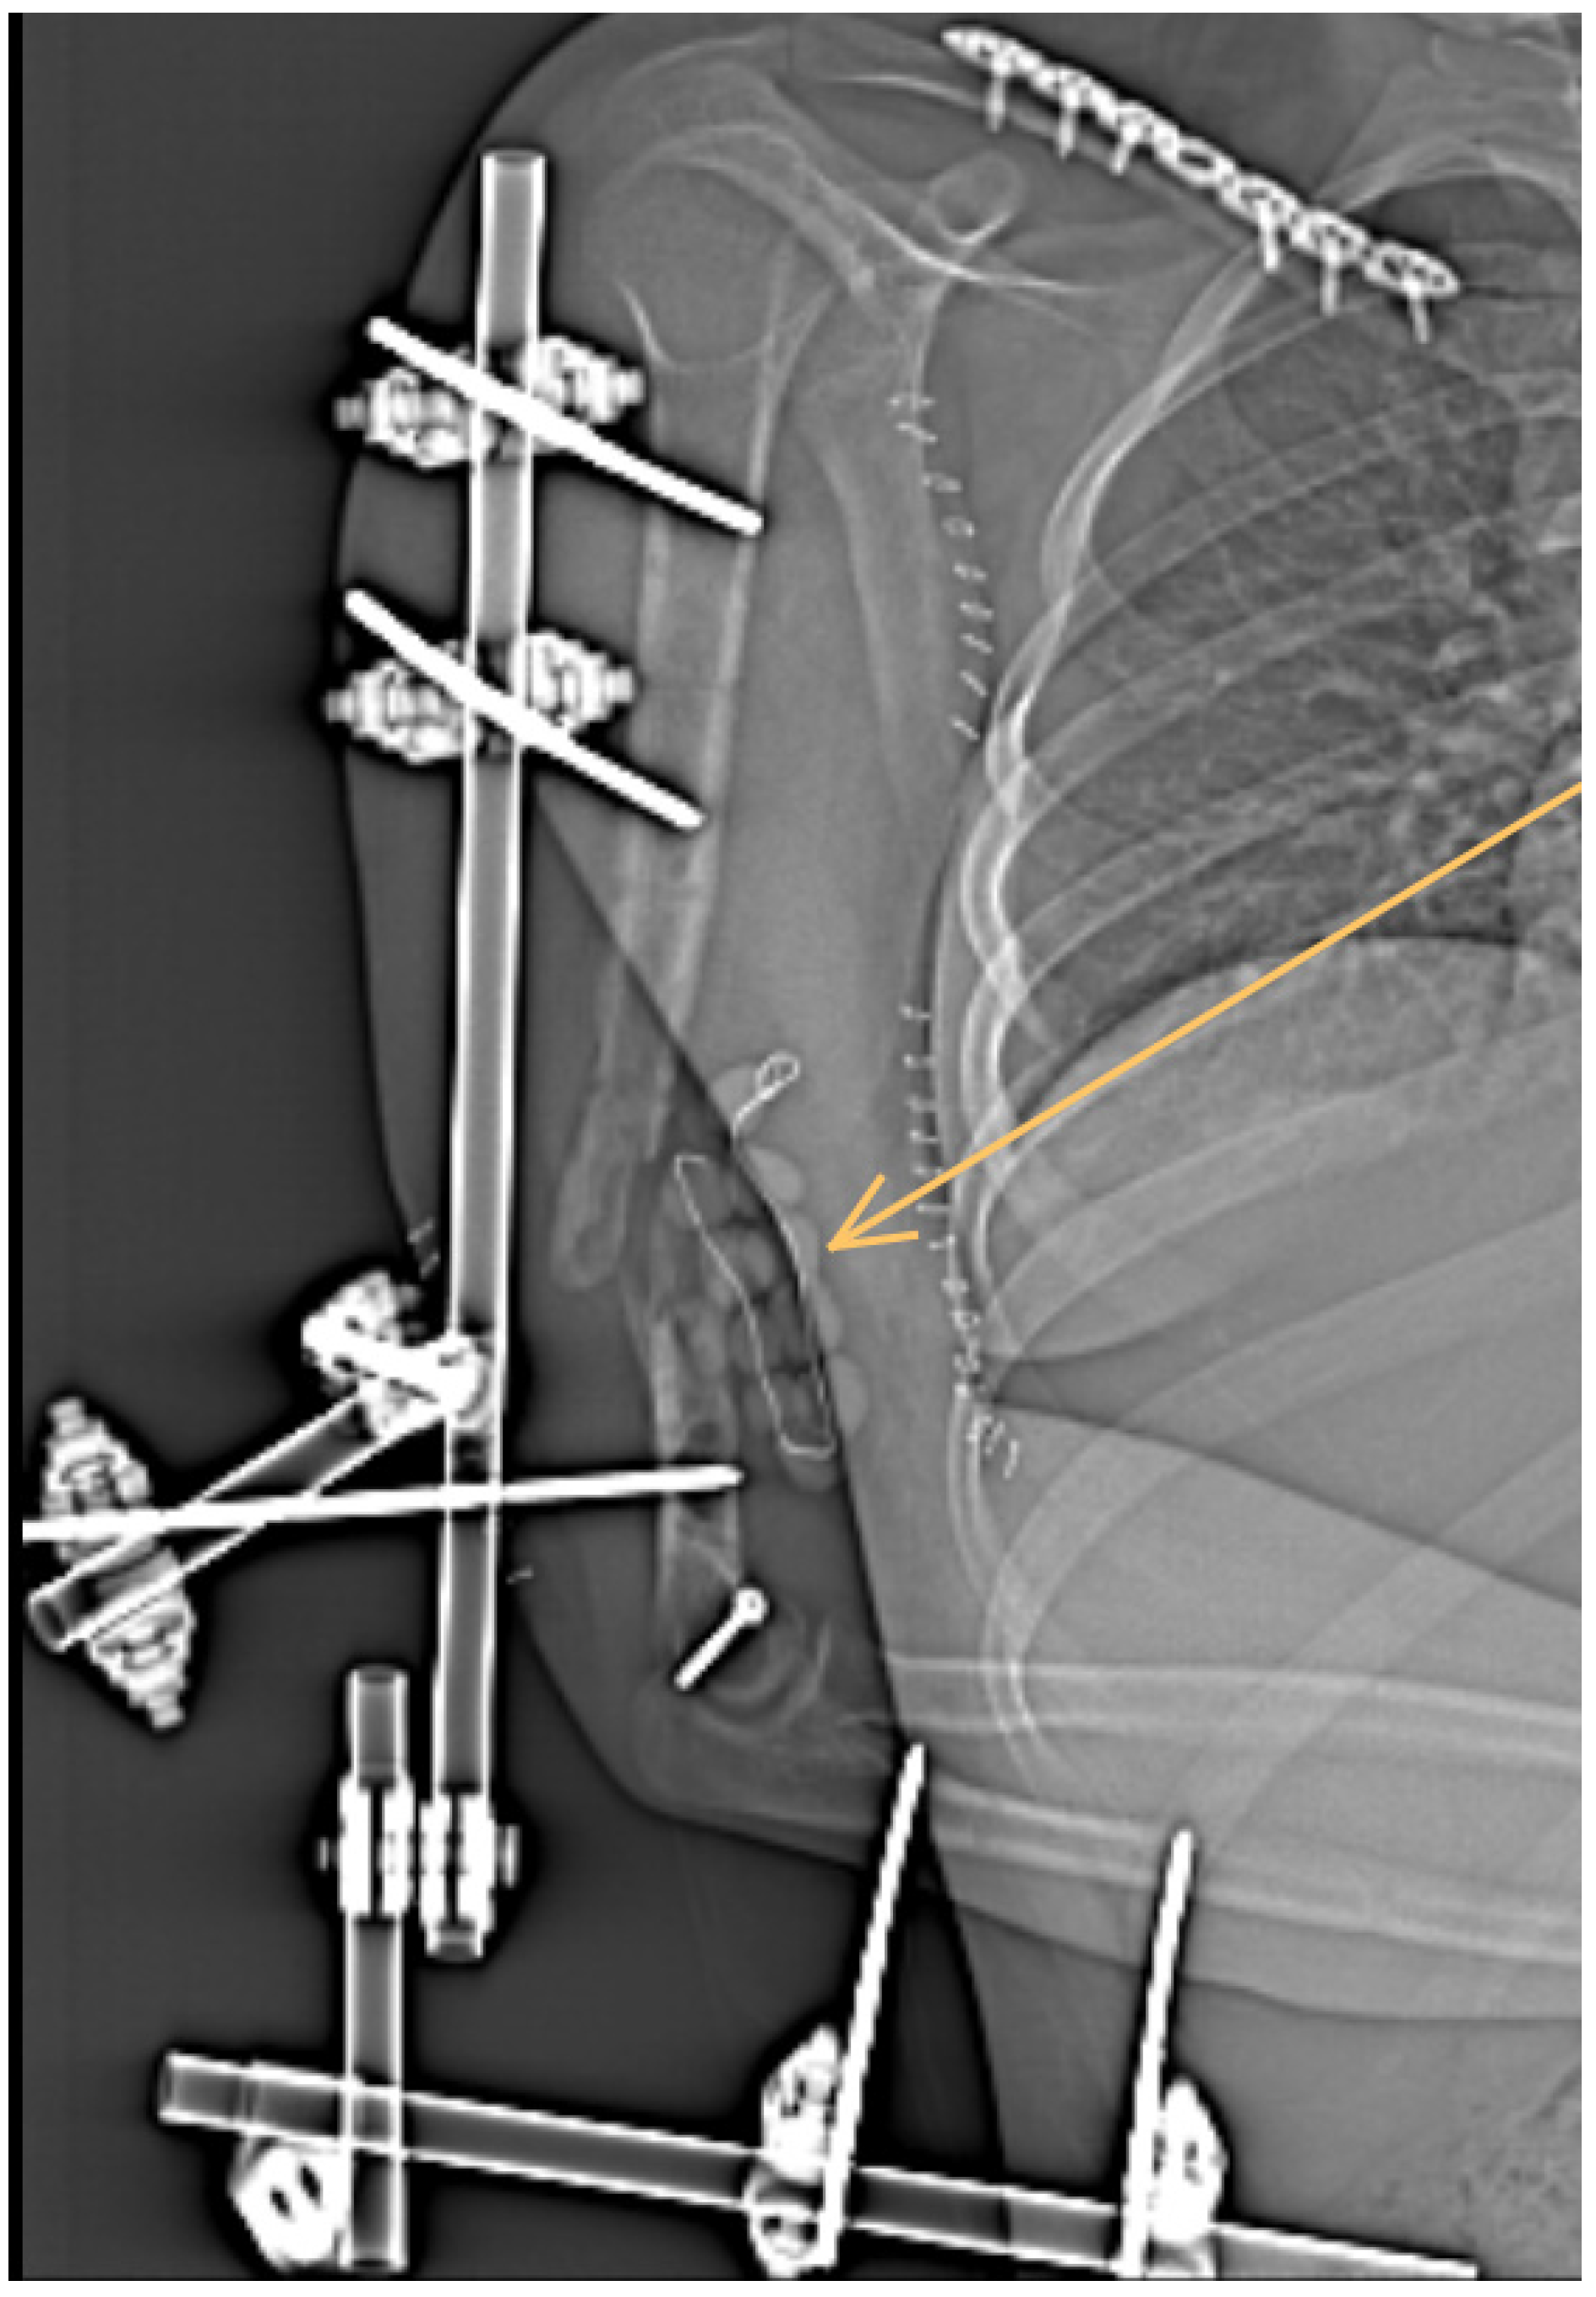

1. Case Report